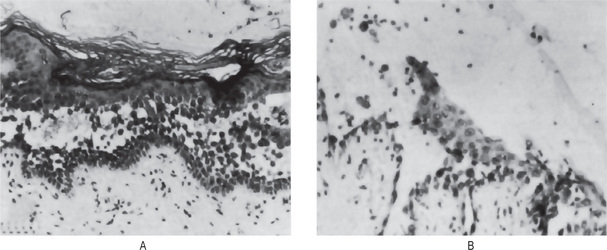

Figure 19-12 Erythema multiforme.

Lesions of the palate (A) and lip (B). B, Courtesy of Meenkashi Ammal Dental College, Chennai

The oral mucous membrane lesions are not usually a significant feature of the disease except for the pain and discomfort they cause. The hyperemic macules, papules or vesicles may become eroded or ulcerated and bleed freely. The tongue, palate, buccal mucosa and gingiva are commonly diffusely involved (Fig. 19-12). Occasionally, mucous membrane lesions occur before the cutaneous manifestations, but oral involvement without dermal lesions has been questioned. Nevertheless, Lozada and Silverman have reported that 12 of 50 patients with erythema multiforme had oral lesions only.

Figure 19-13 Stevens-Johnson syndrome.

Crusting ulcerated lesions of the oral cavity and lips (A), conjunctivitis (B), urethritis (C) are characteristics of the disease.

Eye lesions consist of photophobia, a characteristic of the disease referable to the conjunctivitis, corneal ulceration and panophthalmitis which may occur (Fig. 19-13B). Keratoconjunctivitis sicca also has been described. Blindness may result chiefly from intercurrent bacterial infection.

Genital lesions are reported to consist of a nonspecific urethritis, balanitis and/or vaginal ulcers (Fig. 19-13C).